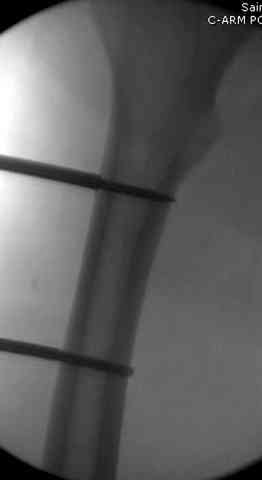

здесь случай с политравмой, перелом зафиксирован  наружным

фиксатором, после третьей irrigation&debridment фиксация бедра

пластиной с последующей кожной пластикой.

Вложение не в текстовом формате было извлечено…

Имя     : 3 open femur crm.jpg

Тип     : image/jpeg

Размер  : 12647 байтов

Описание: отсутствует

Url     : http://weborto.net:8080/pipermail/ortho/attachments/20080516/ebe5bb74/attachment-0013.jpg